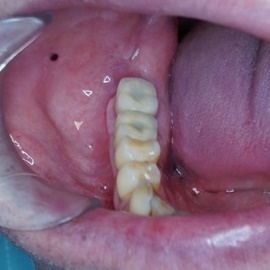

Brakujących pięć zębów dolnych w odcinku wargowym. Rekonstrukcja tkanek i rehabilitacja protetyczna.

Skrócony łuk zębowy, kończący się na trójce. Blade atroficzne tkanki miękkie, relif dziąsła typu A, kość o małej gęstości, słabo ubeleczkowana i o kiepskim ukrwieniu. Niekorzystne warunki do odbudowy kości. Okres leczenia 1,5 roku, po odbudowie kości, zadowalający wynik końcowy w żuchwie, czas na korektę płaszczyzny zgryzowej.